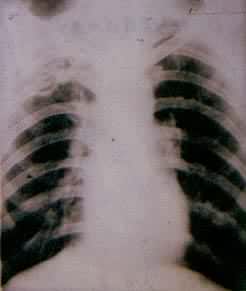

肺部疾病(一) 肺部疾病(二) 大叶肺炎 小叶肺炎 间质性肺炎 肺脓肿(正位) 肺脓肿(侧位) 支气管扩张 浸润性肺结核